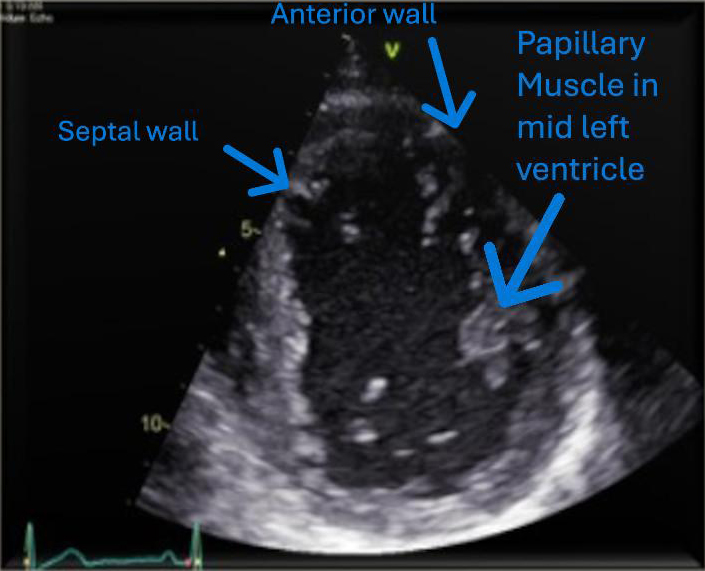

A young man in his early thirties, with a significant medical history of insulin-dependent diabetes mellitus (diagnosed 23 years prior) and ulcerative colitis (diagnosed one year prior), was admitted due to an acute flare-up of ulcerative colitis, characterised by frequent bloody stools and abdominal pain. Despite the initiation of intravenous steroids by the gastroenterology team, he developed symptoms indicative of AMI five days later, confirmed by ST-elevation in the anterior electrocardiogram (ECG) leads (figure 1), and a significant rise in troponin levels, peaking at over 25,000 ng/L. Cardiac echocardiography revealed akinesia of apex, apical inferoseptal and mid-to-apical anteroseptal walls with mildly impaired left ventricular systolic function (figures 2 and 3). Noteworthy was the absence of obstructive atherosclerotic coronary disease in major epicardial vessels, apart from atherothrombotic occlusion in the left anterior descending (figure 4) and diagonal arteries (figure 5), which was addressed with thrombectomy via export catheter, a drug-eluting balloon and intravenous glycoprotein IIb/IIIa inhibitor.